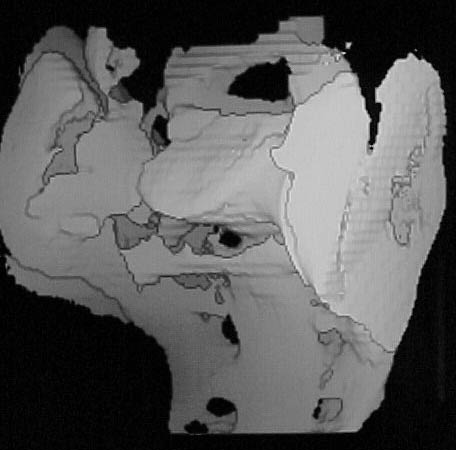

A 28 year old male jumped from the 4th floor on 11-25-2000 sustaining an L1 burst fracture that has been fixed anteriorly by the neurosurgeon with a strut between T12 and L2. A Kaneda device was placed anteriorly as well. My concern is the pelvic ring injury. There are bilateral sacral fractures through the foramen and a transverse element through the sacrum between S2 and S3. the lower part of the sacrum is displaced forward. Anteriorly there are right superior and inferior pubic rami fractures.

3D